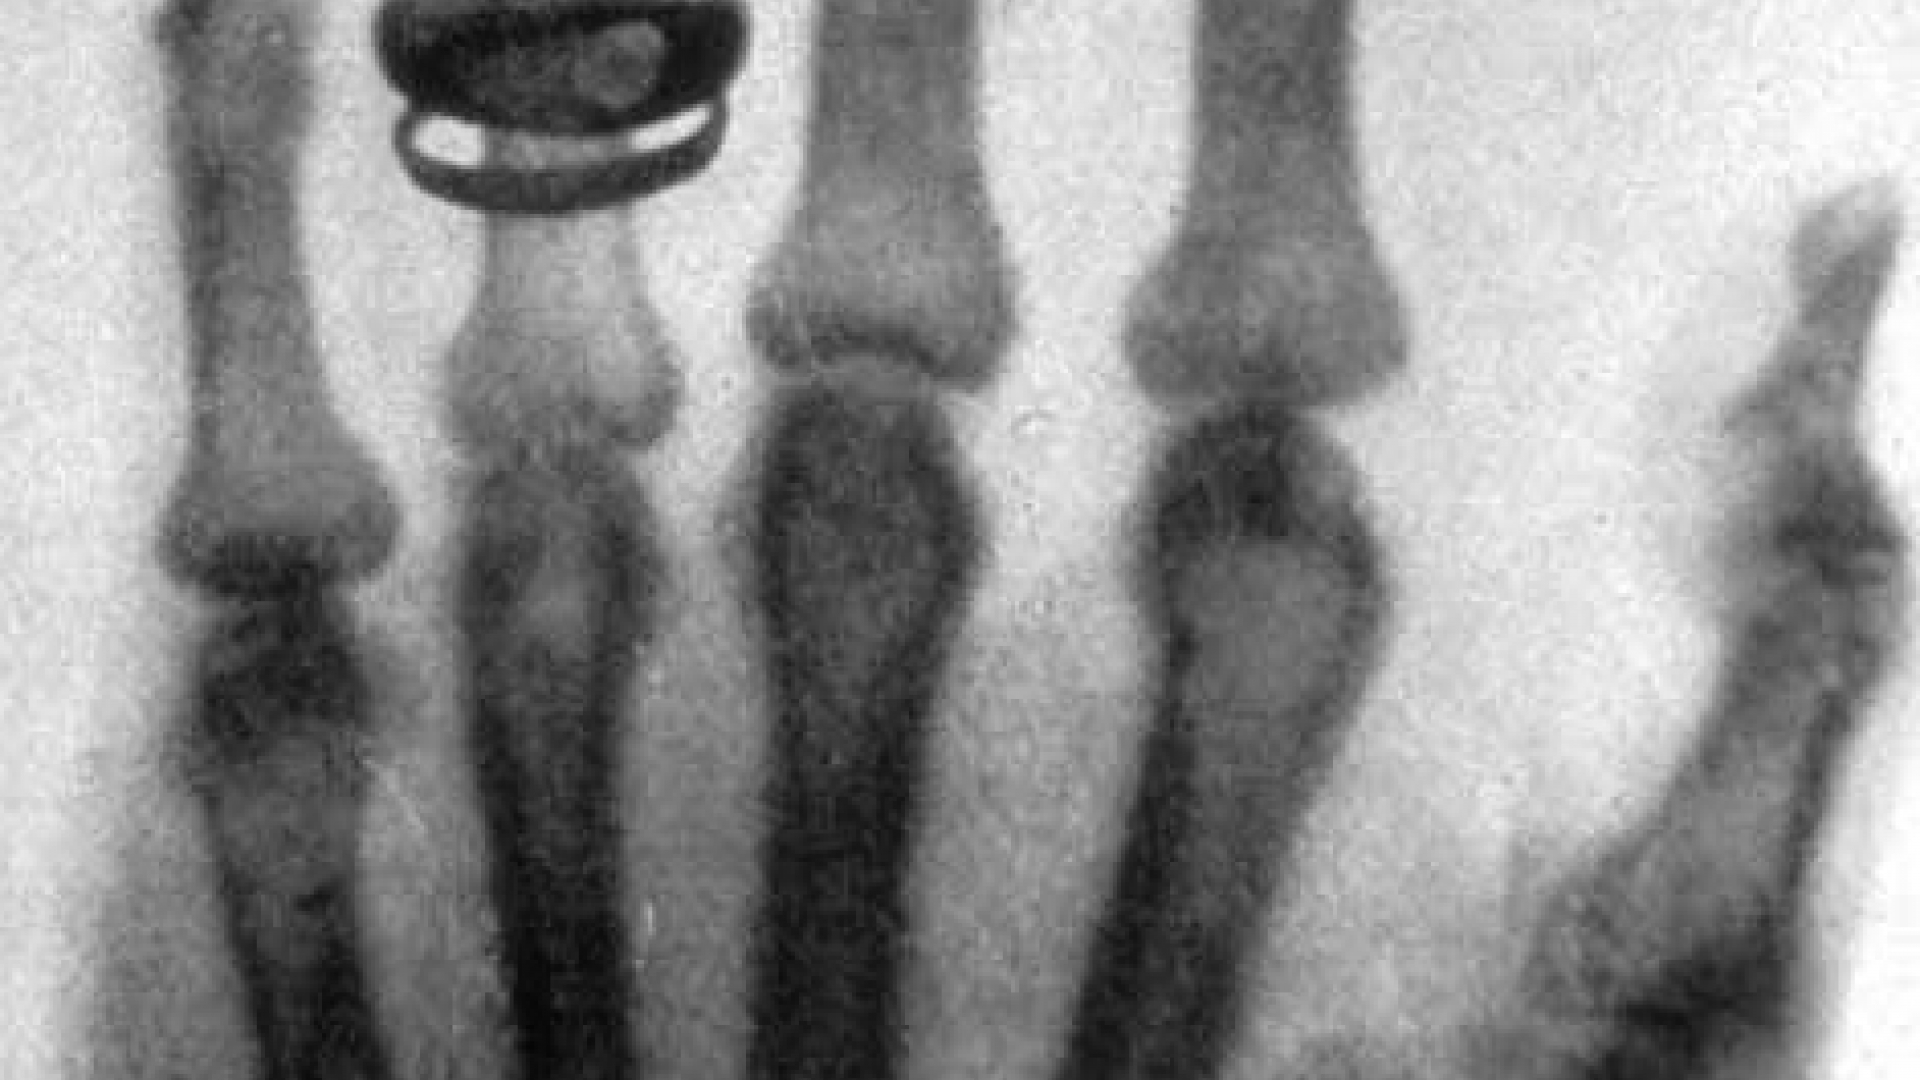

Und noch etwas entdeckt Röntgen beim Experimentieren: Die Strahlung durchdringt sogar den Körper und hinterlässt auf Fotoplatten Abbilder der Knochenstruktur. Der Forscher teilt seiner Frau daraufhin mit: "Ich mache etwas, wovon die Leute, wenn sie es erfahren, sagen werden: 'Der Röntgen ist wohl verrückt geworden.'" Schon bald macht der Physiker die ersten Röntgenbilder, beispielsweise von der Hand seiner Frau. Wenig später veröffentlicht er seine Entdeckung.

Röntgenaufnahme der Hand des Mediziners Albert von Koelliker, der die Umbenennung der X-Strahlen in Röntgenstrahlen vorschlug.

Heute weiß man: Röntgenstrahlung besteht aus elektromagnetischen Wellen – wie das sichtbare Licht auch. Doch die Wellenlänge des Röntgenlichts ist deutlich kürzer, sie liegt im Bereich von 0,001 bis 10 Nanometern. Deswegen durchdringt Röntgenstrahlung viele Materialien, ohne absorbiert oder abgelenkt zu werden – sie flutscht gewissermaßen einfach zwischen den Atomkernen hindurch. Sehr dichte Stoffe mit großen Atomen absorbieren jedoch einen Teil der Strahlung. Deshalb erscheinen die Knochen im Röntgenbild weißlich, das wasserreiche Gewebe um sie herum aber dunkel.